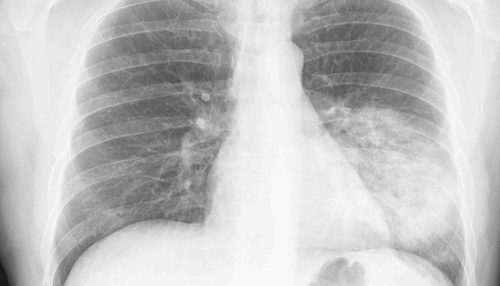

Una vez allí seguramente se le haga una radiografía para detectar si los alvéolos están llenos de líquido de infección, es decir, confirmar si el paciente padece neumonía. También le auscultará, le mirará la temperatura para comprobar que no tenga fiebre y determinará hacer más pruebas en función de lo avanzada que esté la infección.